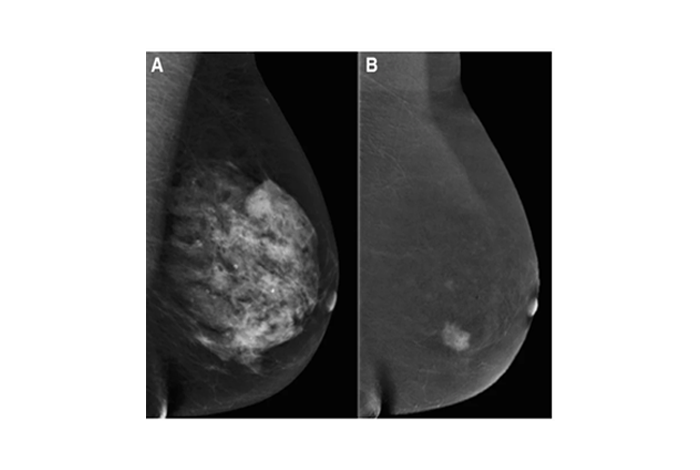

Contrast-Enhanced Mammography (CEM)

• Combines physiological and morphologic imaging using iodinated contrast agents to detect abnormalities such as angiogenesis.

• Offers diagnostic sensitivity and specificity on par with breast MRI but with reduced time and cost.